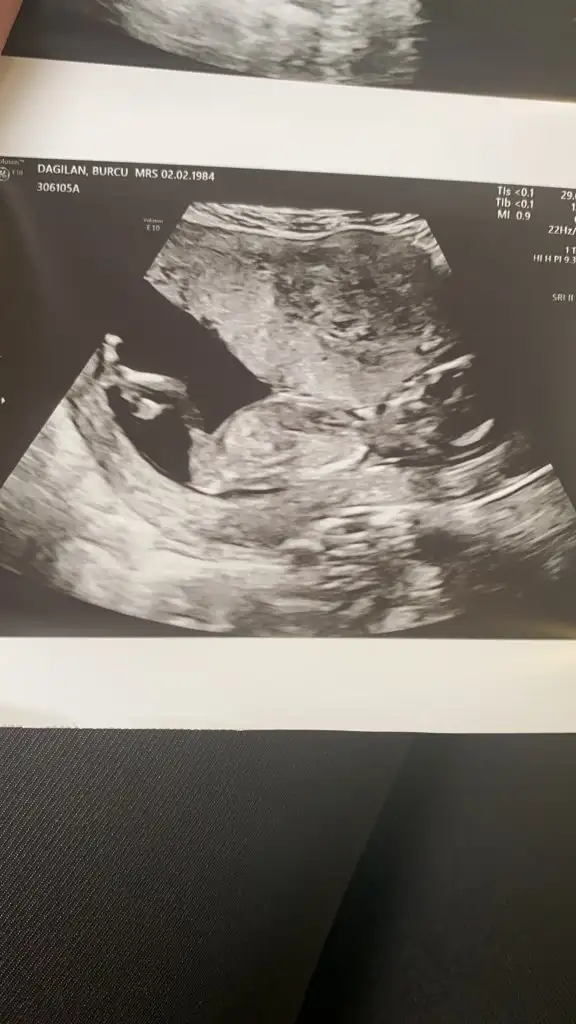

Erkek diyorumIkra meyra banana tahmin yapabilir misiniz?14 haftalık ultrasonŞimdiden teşekkür

Teşekkürler 16 martta belli olacak cinsiyeti mutlaka oylama yapıp size haber vereceğimErkek diyorum